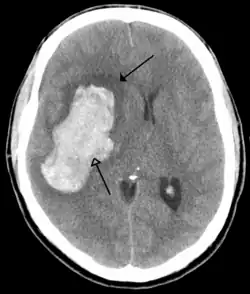

Stroke

A stroke is a decrease in blood supply to an area of the brain causing cell death and brain injury. This can lead to a wide range of symptoms, including the "FAST" symptoms of facial droop, arm weakness, and speech difficulties (including with speaking and finding words or forming sentences).[191] Symptoms relate to the function of the affected area of the brain and can point to the likely site and cause of the stroke. Difficulties with movement, speech, or sight usually relate to the cerebrum, whereas imbalance, double vision, vertigo and symptoms affecting more than one side of the body usually relate to the brainstem or cerebellum.[192]

Most strokes result from loss of blood supply, typically because of an embolus, rupture of a fatty plaque causing thrombus, or narrowing of small arteries. Strokes can also result from bleeding within the brain.[193] Transient ischaemic attacks (TIAs) are strokes in which symptoms resolve within 24 hours.[193] Investigation into the stroke will involve a medical examination (including a neurological examination) and the taking of a medical history, focusing on the duration of the symptoms and risk factors (including high blood pressure, atrial fibrillation, and smoking).[194] Further investigation is needed in younger patients.[195] An ECG and biotelemetry may be conducted to identify atrial fibrillation; an ultrasound can investigate narrowing of the carotid arteries; an echocardiogram can be used to look for clots within the heart, diseases of the heart valves or the presence of a patent foramen ovale.[195] Blood tests are routinely done as part of the workup including diabetes tests and a lipid profile.[195]

Some treatments for stroke are time-critical. These include clot dissolution or surgical removal of a clot for ischaemic strokes, and decompression for haemorrhagic strokes.[196][197] As stroke is time critical,[198] hospitals and even pre-hospital care of stroke involves expedited investigations – usually a CT scan to investigate for a haemorrhagic stroke and a CT or MR angiogram to evaluate arteries that supply the brain.[195] MRI scans, not as widely available, may be able to demonstrate the affected area of the brain more accurately, particularly with ischaemic stroke.[195]